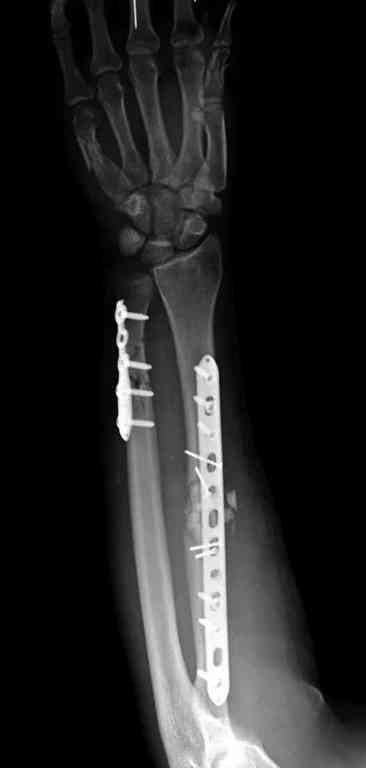

Множественная огнестрельная травма конечностей, перелом костей предплечья, фиксация в первые часы и дефект мягких тканей, мероприятия по закрытию...